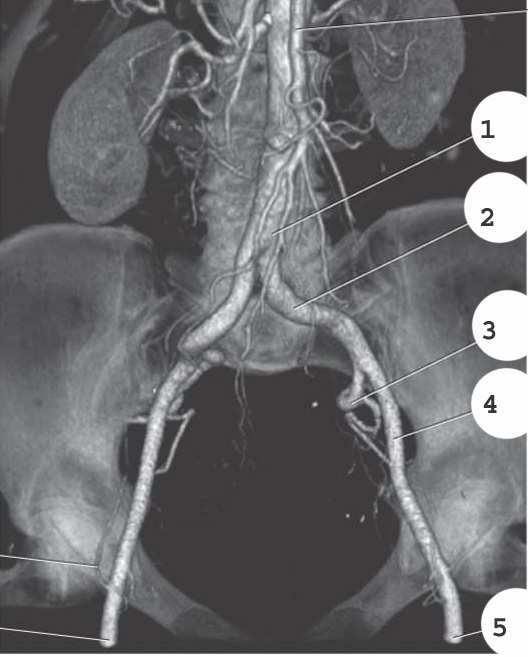

1

femoral head

2

femoral artery

3

femoral vein

4

ligamentum teres

5

gluteus muscles

6

greater trochanter